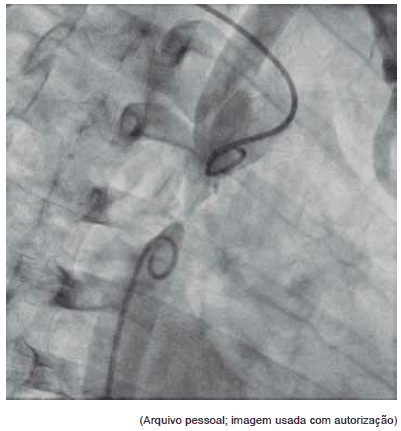

Esta angiografia diz respeito a: